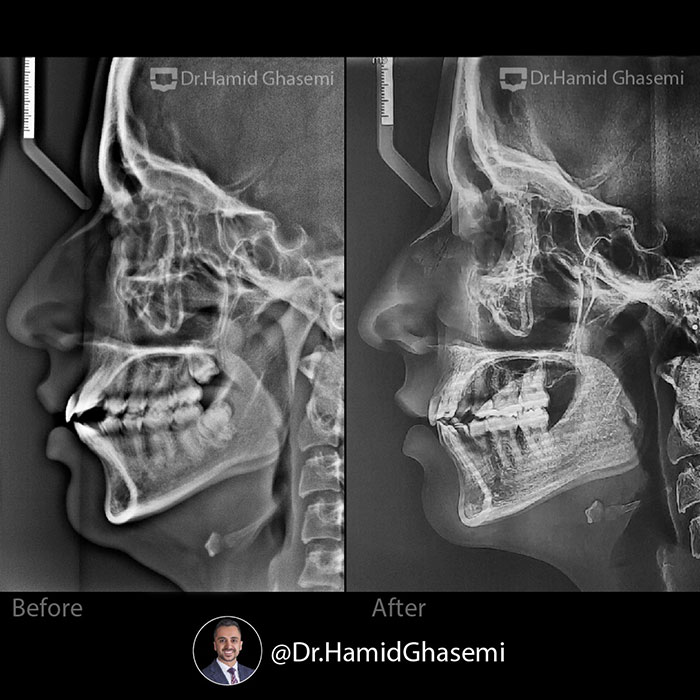

درمان ارتودنسی بدون جراحی در کیس bimaxillary dentoalveolar protrusion (جلوزدگی فک بالا و پایین) با کشیدن دندانهای پرمولر دوم در مدت ۲۰ ماه انجام شد. بهبود بافت نرم صورت و حالت لبها در نمای نیمرخ فتوگرافی و رادیوگرافی لترال کاملا مشهود است.

️Non surgical orthodontic treatment of case with bimaxillary dentoalveolar protrusion done by extraction of 2nd bicuspids within 20 months. Improvement of soft tissue profile and lips posture are obvious in profile photography and lateral ceph xray.